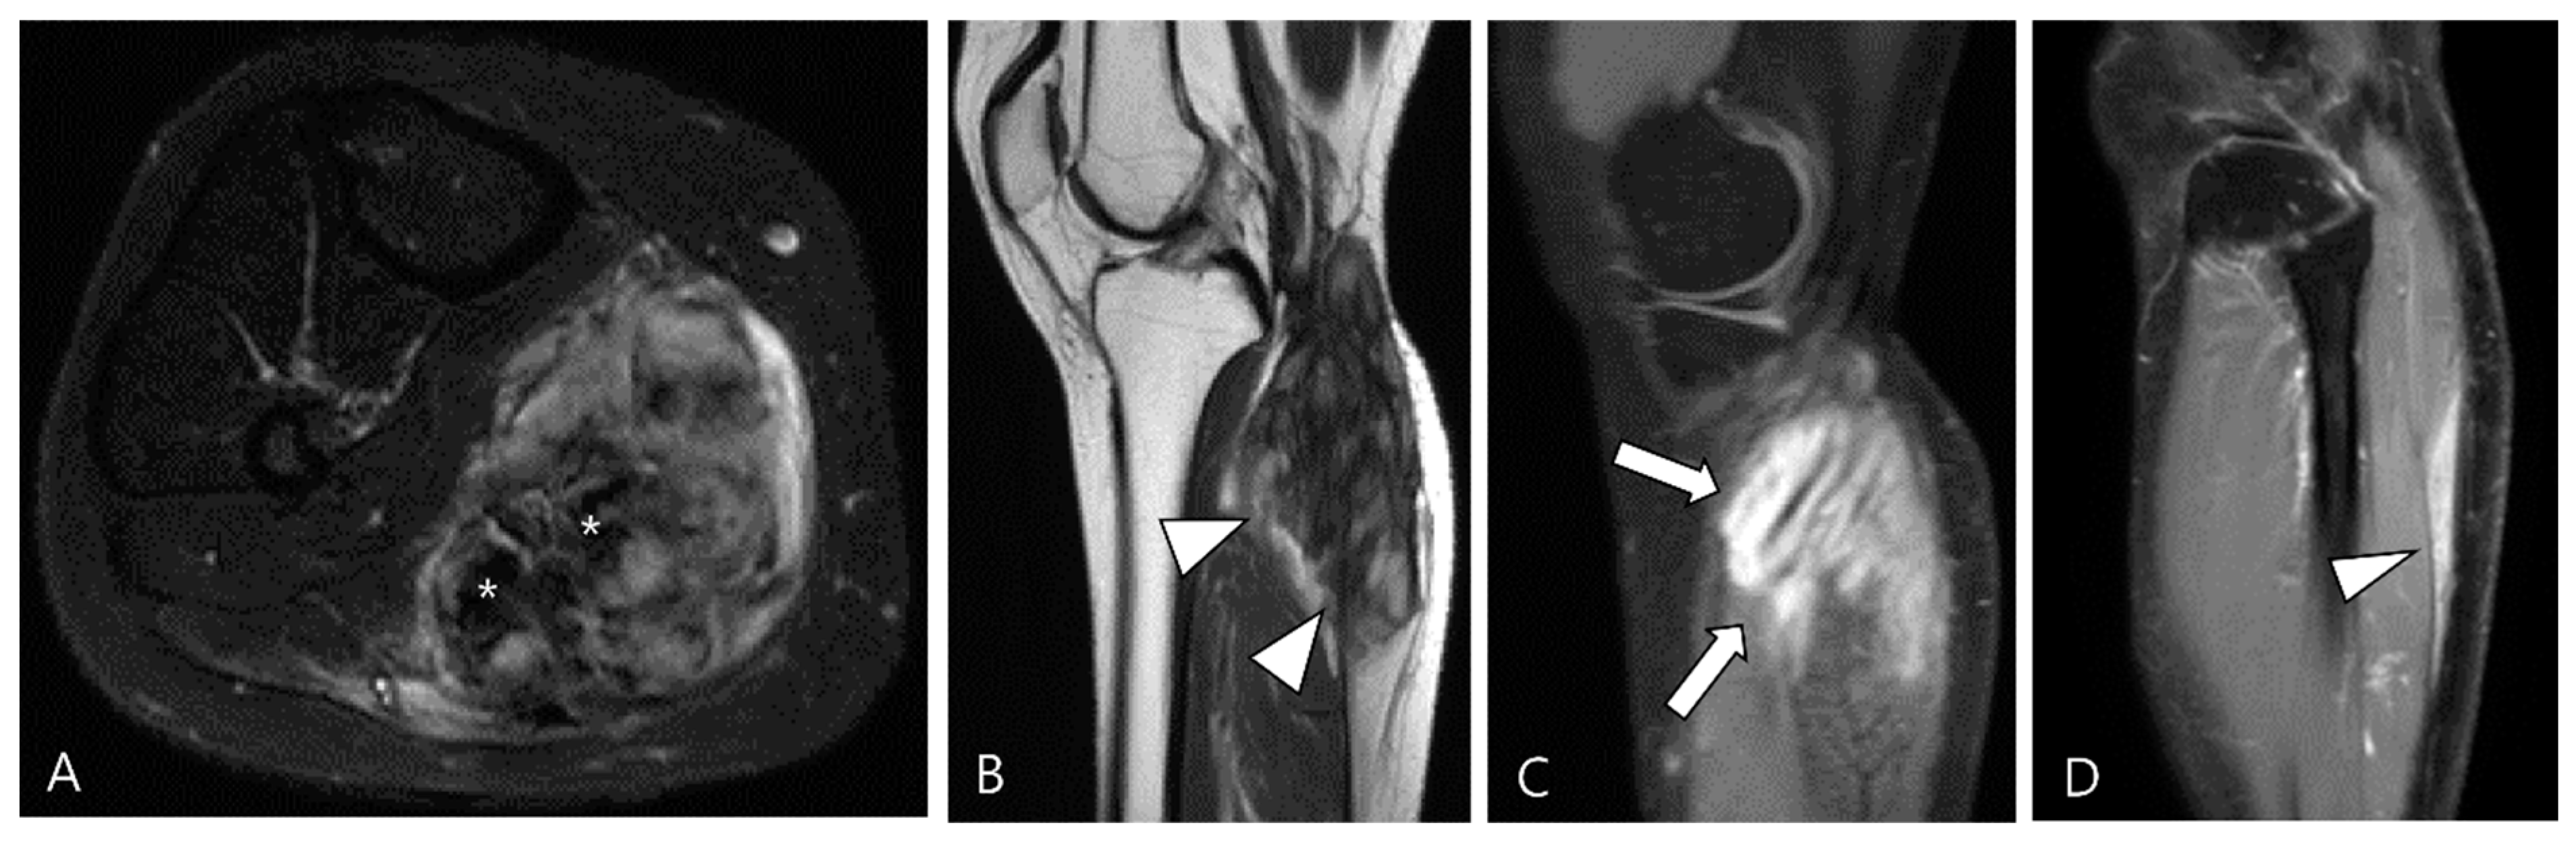

2.3. Morphological Findings for D-TSGCT

2.4. Relationship to Adjacent Structures of D-TSGCT

3.2.1. Fibroma of the Tendon Sheath (FTS)

3.2.2. Extra-Abdominal Desmoid-Type Fibromatosis (DF)